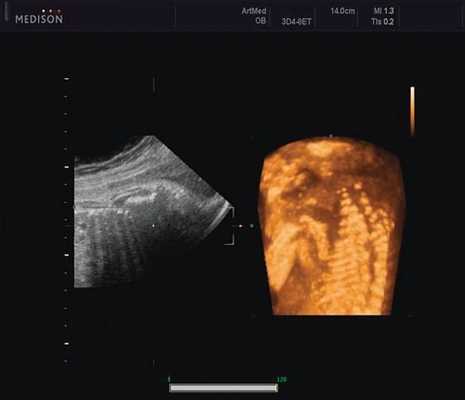

Революцией в пренатальной ультразвуковой диагностике явилось появление объемной эхографии, которая, обладая такими качествами, как неинвазивность, безопасность и возможность многократного применения у одной пациентки, имеет высокую информативность в исследовании анатомии плода и изучении его фенотипа. При применении различных режимов объемной эхографии абсолютно очевидно их преимущество по сравнению с обычным сканированием. Детально можно изучить лицо плода (рис. 1-4) в различные сроки беременности, начиная со сроков первого пренатального скрининга в 11-14 нед, конечности плода, причем не только их наличие и положение (рис. 5, 6), но и состояние и количество пальцев (рис. 7-9) как на руках, так и на ногах. Также можно изучить позвонки плода (рис. 10), состояние твердого нёба (рис. 11, 12), строение наружного уха (ушной раковины) (рис. 13), состояние основных швов черепа и родничков, исключая их преждевременное закрытие при кранисиностозах (рис. 14, 15).

Пациентка К., 26 лет, обратилась в клинику в 23 нед беременности. Беременность первая. Исследование проводилось на аппарате Accuvix-XQ (Samsung Medison) с использованием режима поверхностной объемной реконструкции 3D/4D. Показатели фетометрии полностью соответствовали сроку беременности. В процессе сканирования позвоночника во фронтальной и сагиттальной плоскостях выявлена угловая деформация позвоночника в грудном отделе, протяженностью около трех позвонков. В поперечной плоскости сканирования нарушения структур и целостности тканей не было обнаружено. В режиме 3D/4D реконструкции было выявлено асимметричное расхождение ребер правой и левой стороны грудной клетки (рис. 4).

Ребра левой стороны были сближены, межреберные промежутки уменьшены по сравнению с противоположной стороной (рис. 5, 6). Другой патологии у плода не было выявлено. Заподозрен врожденный сколиоз, основой которого является наличие боковых полупозвонков (hemivertebrae) или боковых клиновидных позвонков. В 26 нед ультразвуковая картина сохранялась. При проведении трехмерной эхографии получено отчетливое изображение асимметрии реберных дуг и сколиотическая деформация позвоночника.